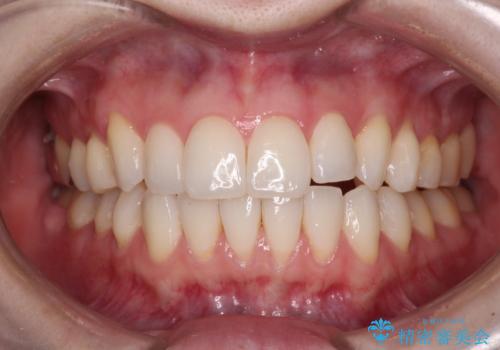

- 前歯のデコボコや八重歯の様になっていることを気にして来院された患者様です。

犬歯捻れて前方に飛び出しており、下顎前歯もそれに沿うようにデコボコとなっていました。

IPR(歯と歯の間を削る処置)によりスペースを獲得して上下顎前歯のデコボコを改善し、前歯が前方に突出しないように設定した上で、インビザラインにて矯正治療を行うこととしました。

途中体調を崩され、長い期間矯正治療を休むことになったため4年半ほどの治療期間がかかりました。